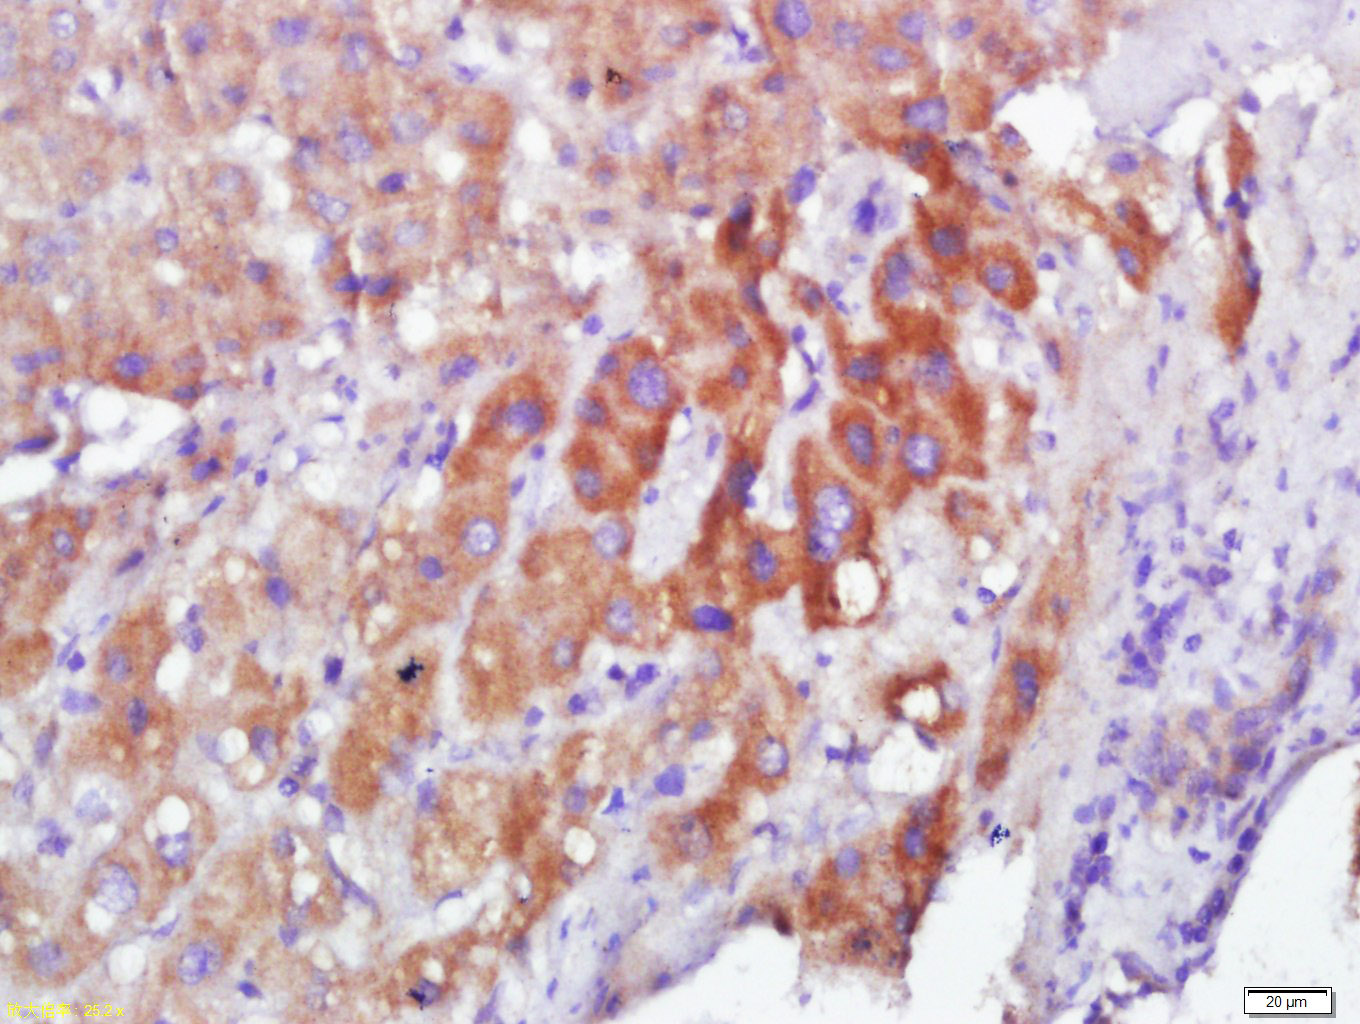

Tissue/cell:Human hepatocellular carcinoma; 4% Paraformaldehyde-fixed and paraffin-embedded; Antigen retrieval: citrate buffer ( 0.01M, pH 6.0 ), Boiling bathing for 15min; Block endogenous peroxidase by 3% Hydrogen peroxide for 30min; Blocking buffer (normal goat serum,C-0005) at 37℃ for 20 min; Incubation: Anti-Calmodulin Polyclonal Antibody, Unconjugated(bs-3666R) 1:400, overnight at 4°C, followed by conjugation to the secondary antibody(SP-0023) and DAB(C-0010) staining